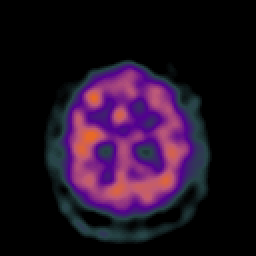

Vascular Malformation (at rest): perfusion SPECT study #1 -- Slice #20

[Home][Help][Clinical] Slice 20